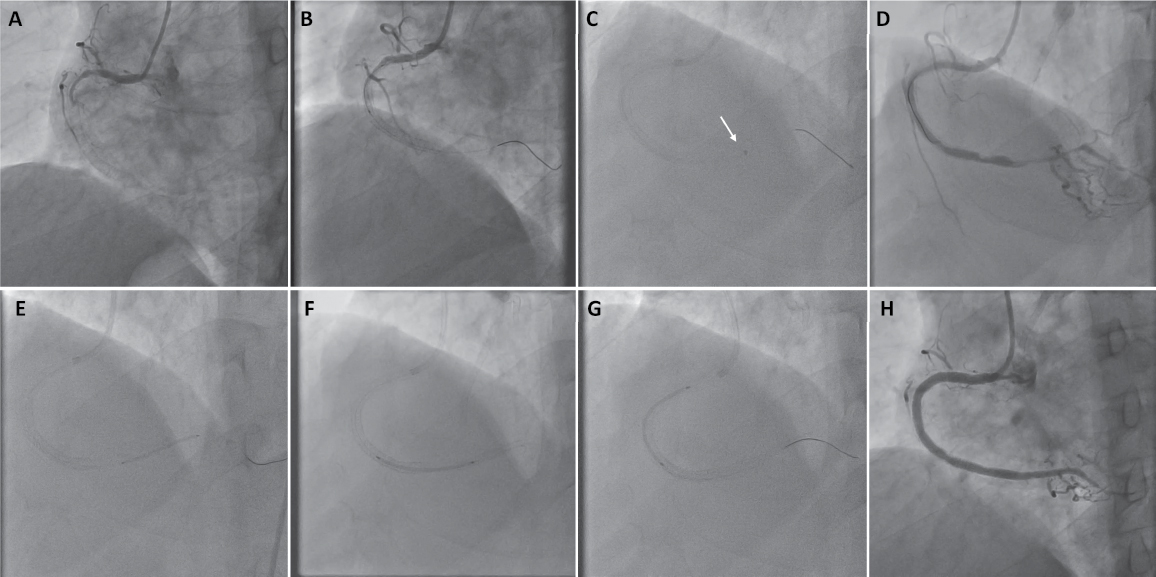

Figure

1. Angiographic images (A to H)

illustrate the procedure as follows: (A) Baseline RCA showing 100%

in-stent restenosis, (B) no-reflow phenomenon following balloon

dilation, (C) Pneumbra-guided thromboaspiration, (D) improved

distal flow, (E & F) drug-eluting stents placement in the distal and

mid segments, (G) drug-eluting balloon treatment in the proximal segment

based on optical coherence tomography findings, and (H) the final

angiographic outcome of the RCA.

The

procedural strategy employed a retrograde approach using a Fielder XT-A wire

and Finecross microcatheter, achieving true lumen re-entry after initial

subintimal tracking. Predilation with a 2.0 mm semi-compliant balloon failed to

restore distal flow (TIMI-1), prompting suspicion of neoatherosclerotic debris

or thrombus.

The 5.3 Fr catheter’s sustained negative suction (-29 mmHg) and

exceptional trackability enabled seamless navigation through the previously stented RCA, aspirating

dense, organized thrombus despite the lesion’s chronicity. Its maneuverability

proved critical in traversing calcified segments, achieving TIMI-2 flow

post-aspiration. Subsequent OCT imaging (Ultreon 2.0) revealed layered,

heterogeneous tissue in the proximal RCA (Wataru-Yamamoto Type 4 ISR) with

invisible struts and neointimal rupture, indicative of organized thrombus. Distally, fibroatheroma with minimal calcification (Gonzalo’s classification: heterogeneous, noncalcified) was identified. Tailored therapy included deployment of

a 3.0 × 28 mm drug-eluting stent (DES) at the fibroatheroma site, application of a 4.0 × 35 mm drug-eluting balloon (DEB) to the NIH-dominant segment, and high-pressure post-dilation with a 4.5 mm noncompliant balloon.